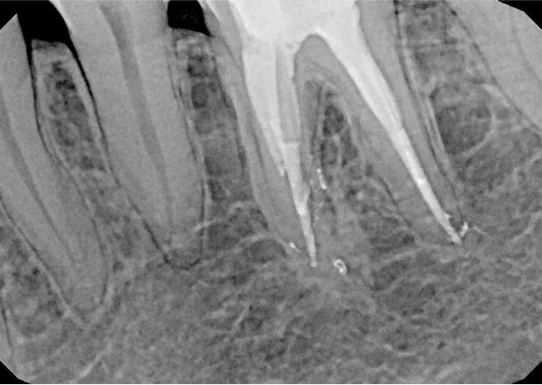

Po zakończonym leczeniu kanałowym, wykonujemy kontrolne zdjęcie RTG. Pozwala ono na natychmiastową ocenę jakości wypełnienia kanałów korzeniowych i potwierdzenie skuteczności przeprowadzonego zabiegu. Dla nas leczenie kanałowe Opole to synonim precyzji i pewności.

Na podstawie zdjęcia rentgenowskiego określa się kształt i długość kanału bądź za pomocą specjalnego urządzenia mierzy się jego długość. Potem lekarz otwiera wejścia do kanału, chroniąc ząb koferdamem, czyli specjalną gumą, zapewniającą sterylność oraz chroniącą przed środkami chemicznymi służącymi do oczyszcza-nia kanału. Używa się do tego zarówno specjalistycznego sprzętu, jak i nowo-czesnych mikroskopów, pozwalających na uzyskanie dokładnego obrazu leczone-go zęba. Ostatnią czynnością jest wypełnienie materiałem światłoutwardzal-nym i zabezpieczenie zęba przed dostaniem się i rozwojem bakterii mogących wywołać wtórny stan zapalny.

Przed rozpoczęciem leczenia kanałowego kluczowa jest dokładna diagnostyka. Zazwyczaj wykonujemy kontrolne zdjęcia RTG, a czasem nawet kilka, aby precyzyjnie ocenić stan zęba i otaczających go tkanek. W bardziej skomplikowanych przypadkach możemy zlecić wykonanie tomografii komputerowej (CBCT) dla uzyskania trójwymiarowego obrazu.

Nasza diagnostyka to nie tylko cyfrowe zdjęcia RVG (radiowizjografia), które ograniczają dawkę promieniowania i dają natychmiastowy obraz. W skomplikowanych przypadkach kierujemy pacjentów na tomografię komputerową CBCT, która daje trójwymiarowy obraz struktur zębowych i kostnych, co jest nieocenione przy planowaniu trudnego leczenia kanałowego lub ponownego leczenia endodontycznego.